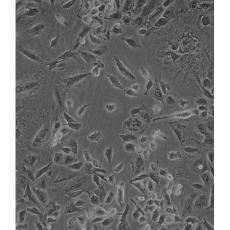

NCI-H1975

中文名稱 人肺腺癌細(xì)胞

組織來源 肺腺癌;女性

生長特性 adherent

形態(tài)特征 epithelial

細(xì)胞描述 該細(xì)胞是1988年7月從一名女性(無抽煙史)非小細(xì)胞肺腺癌組織中分離得到的。